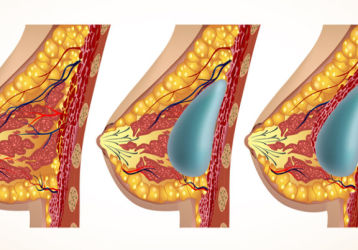

Что такое капсулярная контрактура — признаки, причины, лечение

Что такое капсулярная контрактура. Причины возникновения, как лечится осложнение. Методы полноценной диагностики и хирургического лечения.